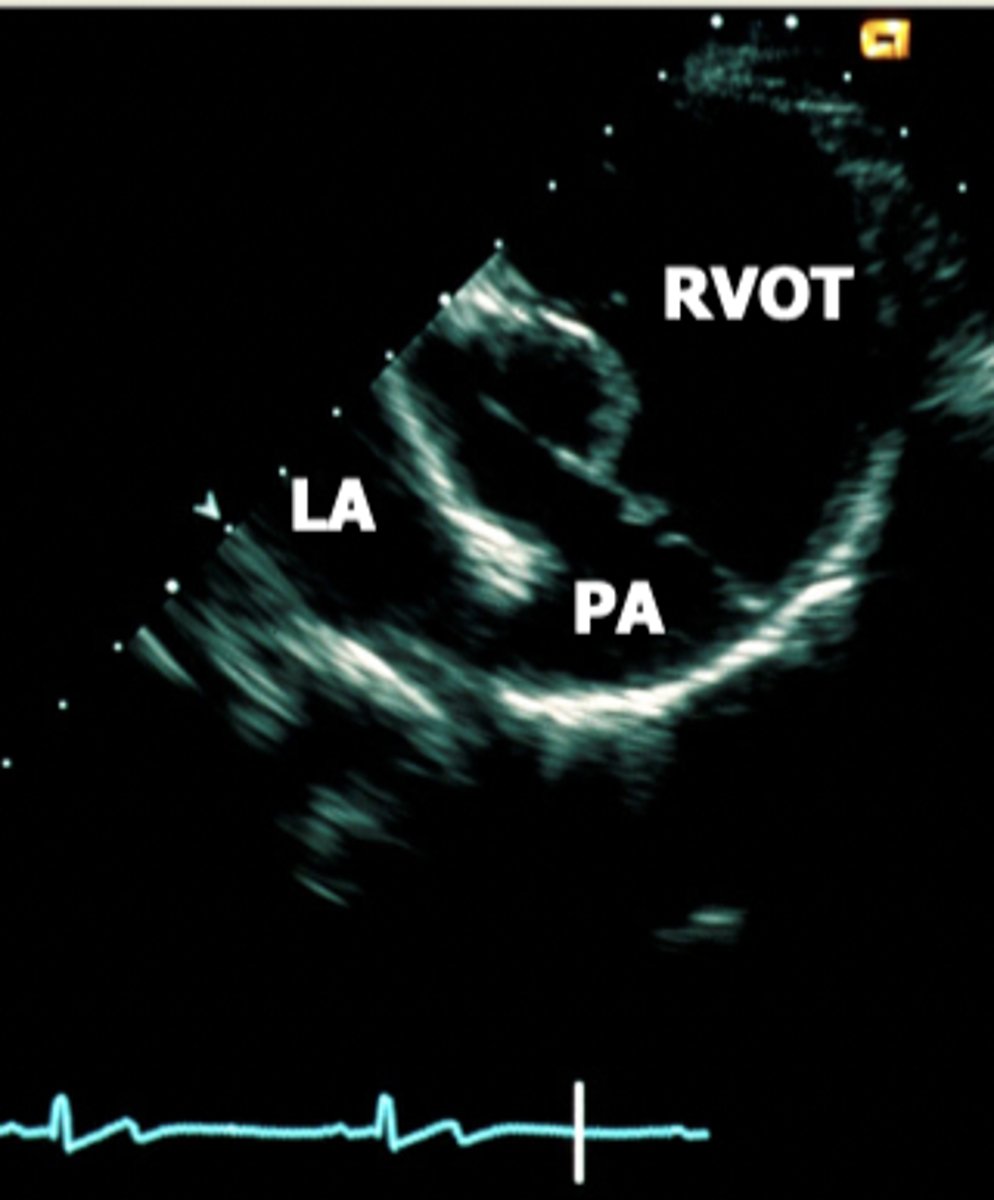

right parasternal subcostal view

view that best aligns with direction of the blood flow; used to truly measure velocity

left parasternal apical view

used for four chamber or five chamber view when the dog in on their left side